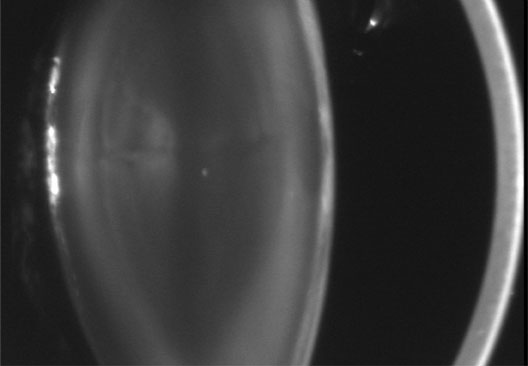

Neurofibromatosis 2 (NF2) is an autosomal-dominant (AD) disorder caused by mutations that inactivate the NF2 tumor suppressor gene. Multiple central and peripheral nervous system tumors and ocular abnormalities are common in NF2, and bilateral vestibular schwannomas (acusticus neurinoma) are pathognomonic for the disease. Constitutional nonsense or frameshift NF2 mutations are associated with severe NF2 (i.e., earlier onset of symptoms and more tumors), splice site mutations with variable disease severity, and missense mutations with mild disease. Cataracts are the most common nontumor and ocular manifestation in NF2, and are prevalent in about 60% to 80% of NF2 patients. In animal models, lens fiber cells that are more differentiated express less NF2 protein than the epithelial regions of the lens, which suggests that the NF2 protein may play a role in lens epithelial cell migration or elongation. In one study,8 the overall prevalence of cataracts in NF2 was 33%, but was significantly lower in patients with somatic mosaics and in individuals with new, as yet unknown mutations, and onset of symptoms above the age of 20 years than in patients with classic NF2, nonsense, or frameshift mutations. Of the NF2 patients with cataracts in that study, 29% were diagnosed with cataracts at an age below 10 years, and 47% were diagnosed under the age of 20 years. In 70% of the patients cataract diagnosis preceded nonocular signs or symptoms of NF2. Cataracts typically present as posterior subcapsular plaque-like opacities (Figs. 3 and 4). Other ocular manifestations include retinal hamartomas, optic nerve sheath tumors, fibrotic maculopathies, and perineural calcification of the optic nerve.9

Fig. 4. NF2. Paracentral plaque-like retrolental opacity of NF2 in retroillumination view. (Courtesy of Dr. F.D. Ellis, Zionsville, Indiana.)